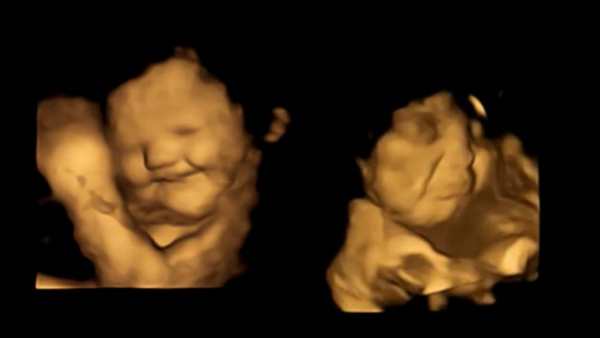

அதில் விரும்பிய உணவை தாய் உண்ணும் போது, சிசுக்கள் சிரித்த முகத்துடனும், பிடிக்காத உணவை உண்ணும் போது சிசுக்கள் தங்கள் முகத்தை அஷ்டக்கோணலாகவும் மாற்றுவதை மருத்துவர்கள் வீடியோ பதிவு செய்துள்ளனர்.

பின்னர் 20 நிமிடங்கள் கழித்து இந்தப் பெண்களின் வயிற்றில் உள்ள சிசுக்களை 4D ஸ்கேன்களை கொண்டு விஞ்ஞானிகள் பார்த்தனர். அப்போது கேரட், பீட்ரூட், சப்போட்டா போன்ற இனிப்புச் சுவை மிகுந்த பழங்களை சாப்பிட்ட பெண்களின் சிசுக்கள் நன்றாக சிரித்துக் கொண்டும், ஜாலியாக அங்கும் இங்கும் அசைந்து கொண்டும் இருக்கின்றன. அந்த சிசுக்களின் முகத்தில் குறைந்தது அரை மணிநேரமாவது சிரிப்பு இருக்கிறது.

அதே சமயத்தில், கீரை, காய்கறிகள் கொடுக்கப்பட்ட பெண்களின் சிசுக்கள் தங்கள் முகத்தை அஷ்டக்கோணலாக வைத்திருந்தன. அதை பார்க்கும் போது சிசுக்கள் கோபமாகவும், வெறுப்பாகவும் இருப்பது நன்றாக தெரிகிறது. மேலும், பெரிய அளவில் அசைவும் இல்லாமல் கடமைக்கு உடலை நெளித்துக் கொண்டு இருந்தன. இந்த வெறுப்புணர்ச்சி பல மணிநேரங்களுக்கு இந்த சிசுக்களிடம் காணப்பட்டது. குறைந்தது 2 மணிநேரங்களுக்கு பிறகுதான் இந்தக் குழந்தைகள் அந்த வெறுப்புணர்வில் இருந்து வெளியே வருகின்றன.

மேலும், வயிற்றில் இருக்கும் சிசுக்கள் தங்கள் உணர்ச்சிகளை காட்டும் புகைப்படங்களையும், வீடியோக்களையும் மருத்துவர்கள் வெளியிட்டனர். இந்த புகைப்படங்கள் சமூக வலைதளங்கில் வைரலாகி வருகின்றன.